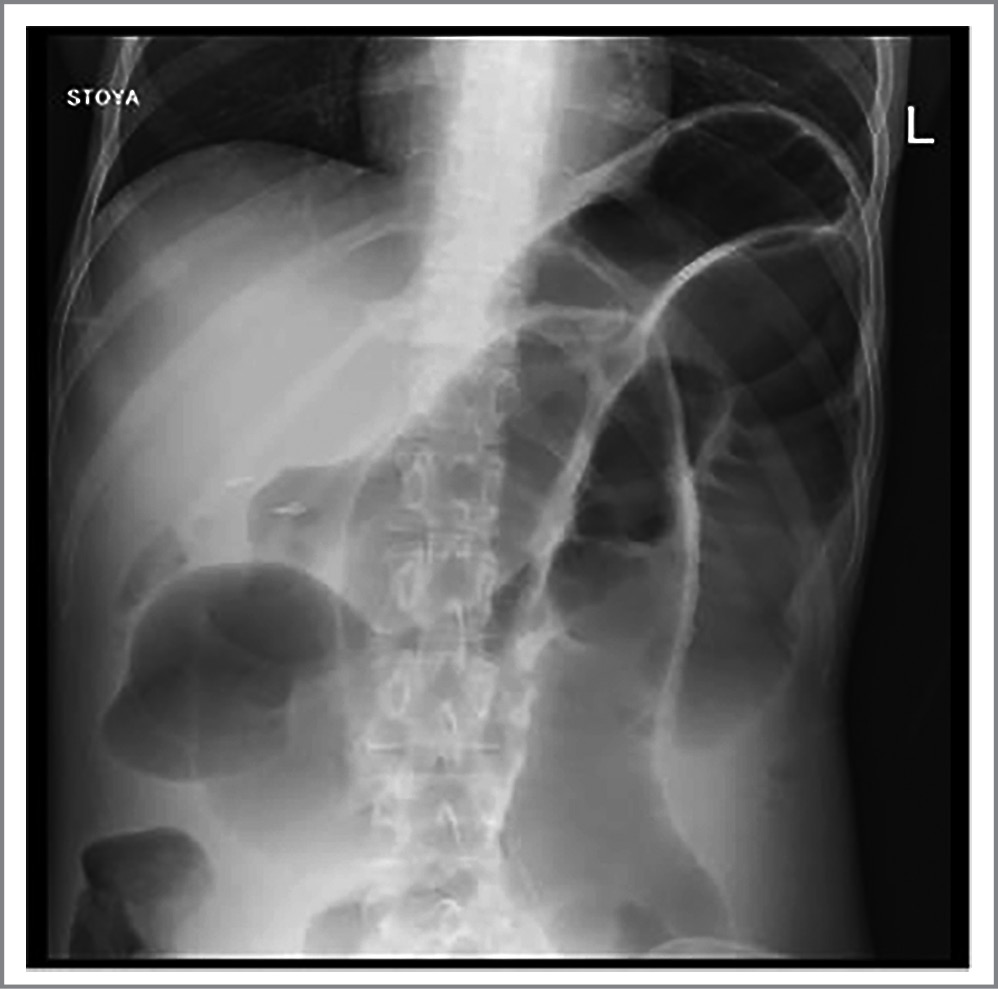

Рис. 5. Рентгенологическая картина брюшной полости у больной А. после 5 мес лечения.

Fig. 5. X-ray image of the abdominal cavity in patient A. after 5 months of treatment.

Эффективность терапии оценивали по данным рентгенологического исследования с контрастированием желудочного и интестинального зондов. На протяжении всего периода наблюдения происходило постепенное уменьшение просвета желудка, двенадцатиперстной и начального отдела тощей кишки до 2–2,5 см. Средние и дистальные отделы ТК оставались расширенными до 7 см (рис. 5). Перистальтика отсутствовала на всем протяжении ТК, что подтверждало тяжелую форму интестинальной псевдообструкции. Попытки восстановить моторику ее регуляторами – метоклопрамидом, домперидоном и итопридом не оказывали эффекта. Тегасерод и прукалоприд – селективные агонисты серотониновых рецепторов – вызывали сильные боли в животе и были отменены.